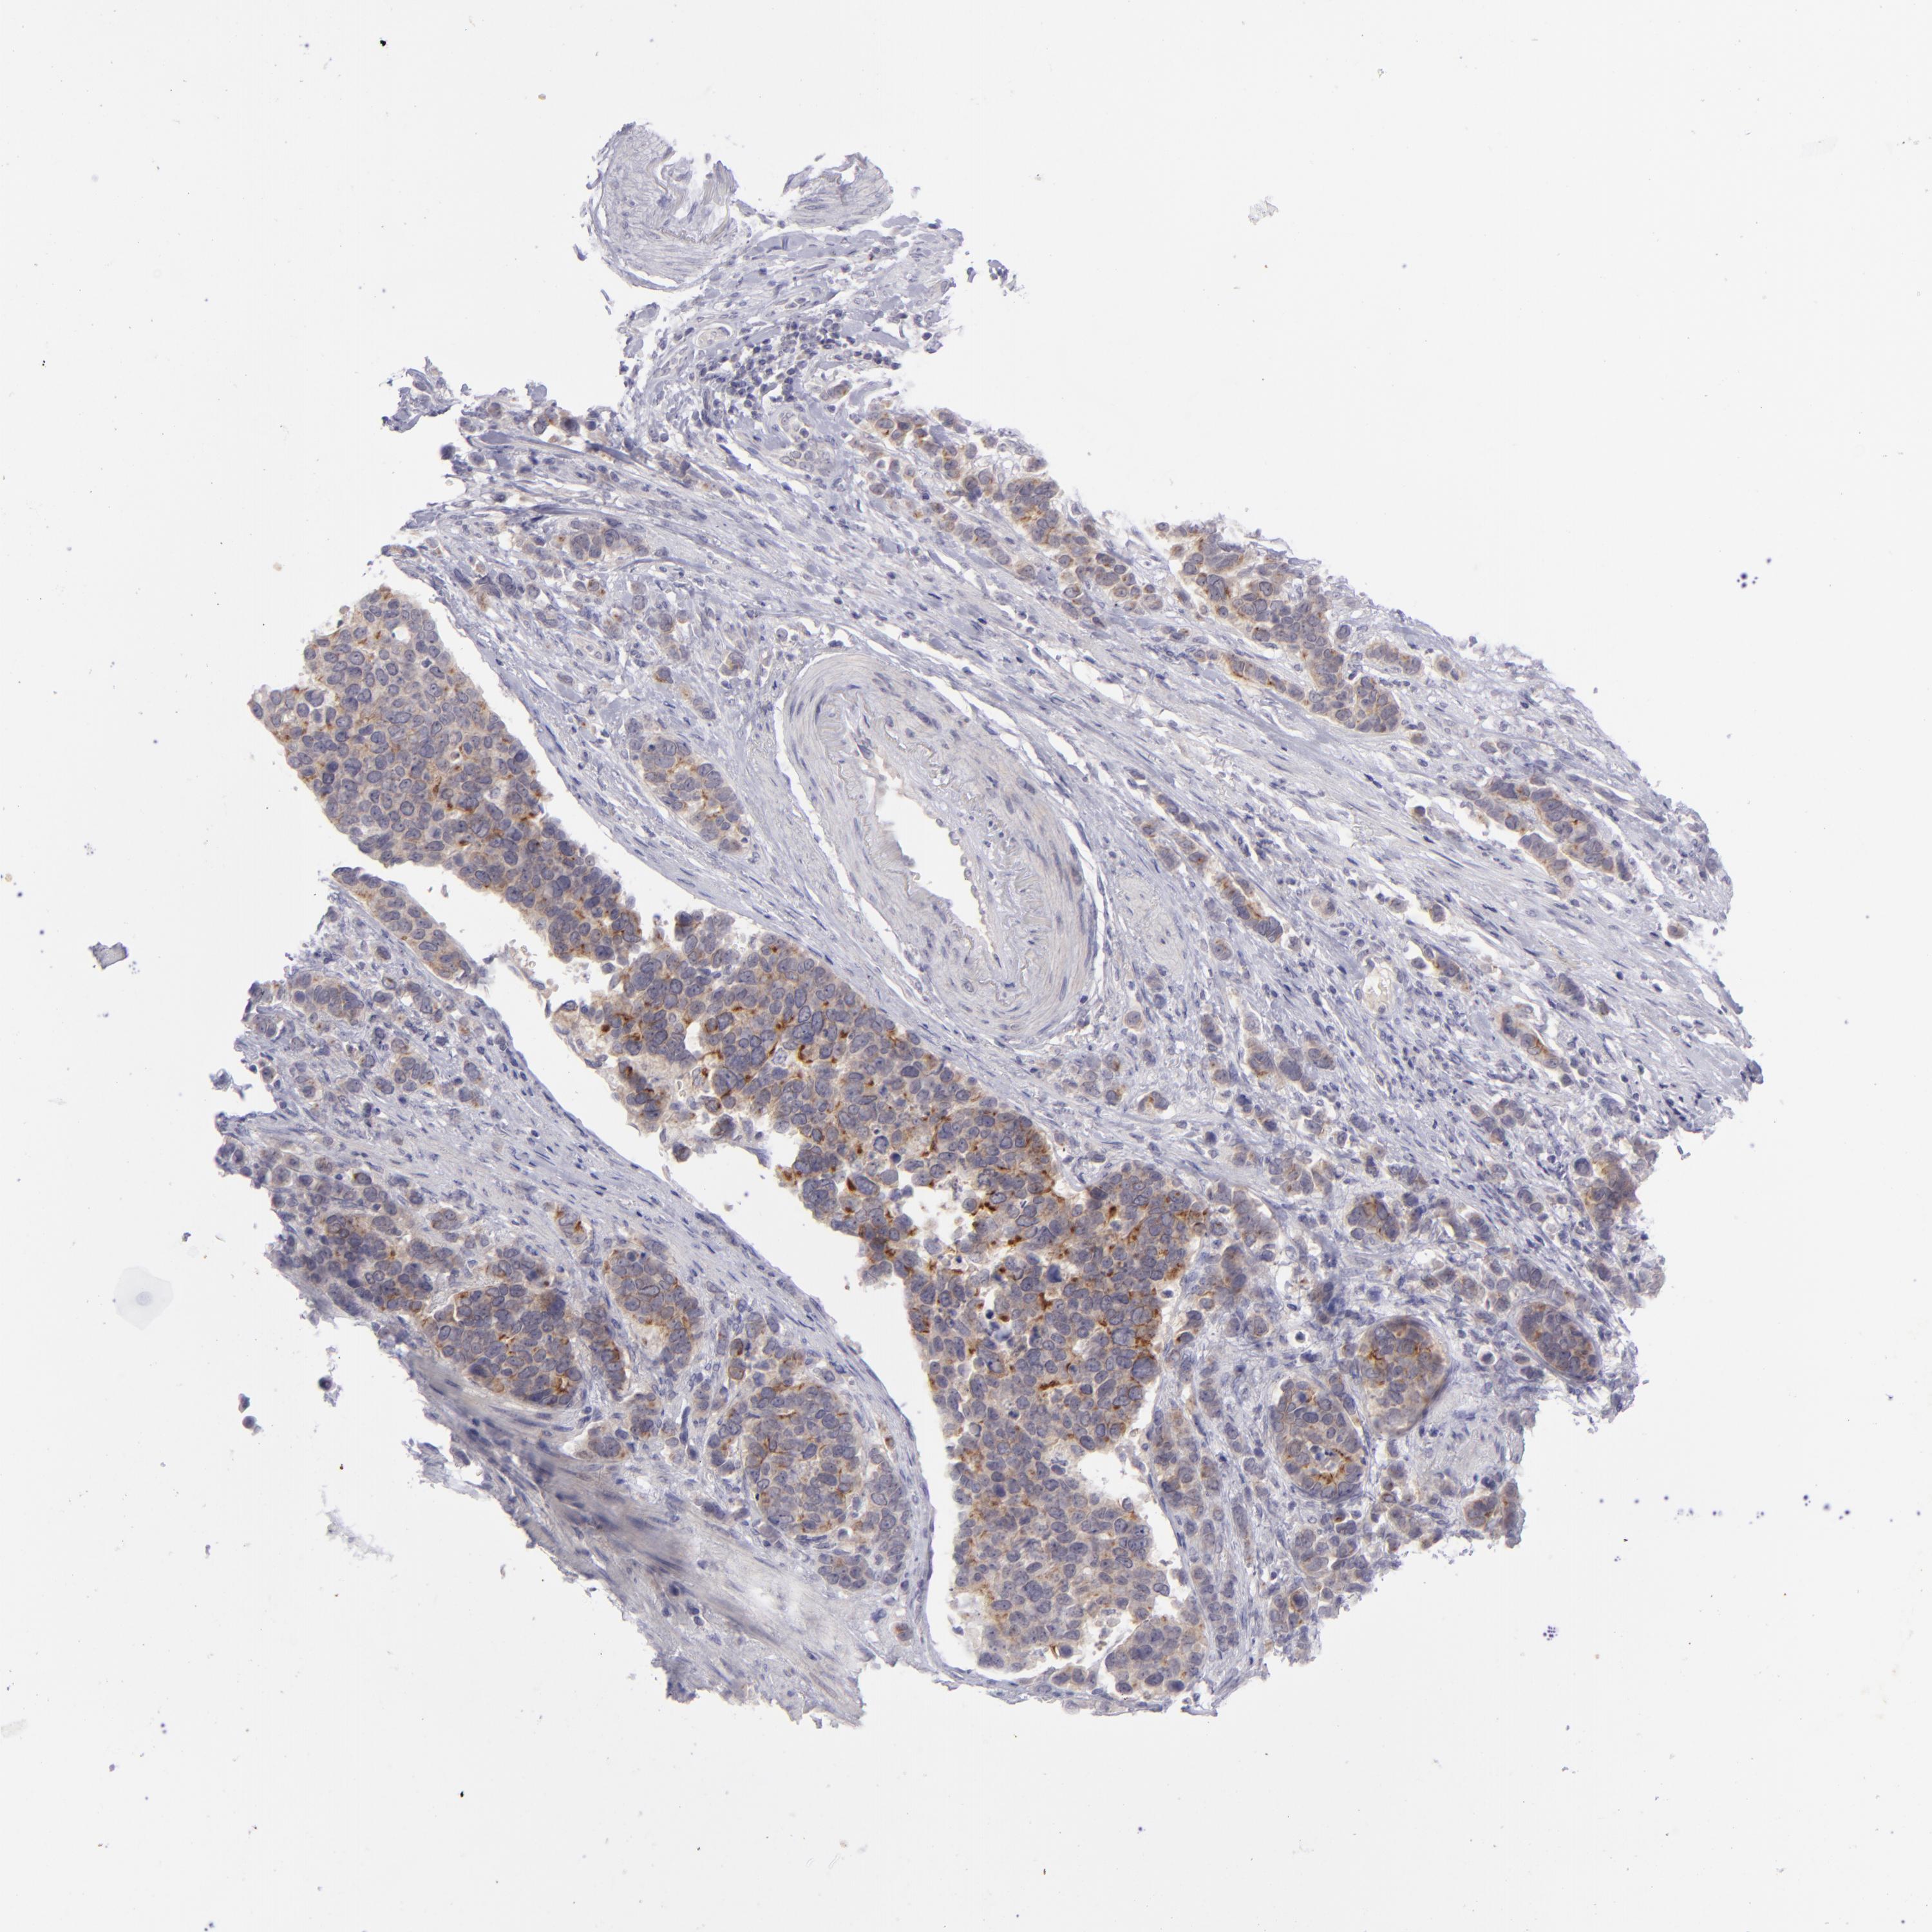

STOMACH CANCER - Protein expressioni

A mouse-over function shows sample information and annotation data. Click on an image to view it in a full screen mode. Samples can be filtered based on level of antibody staining by selecting one or several of the following categories: high, medium, low and not detected. The assay and annotation is described here.

Antibody stainingi

Antibody staining in the annotated cell types in the current human tissue is reported as not detected, low, medium, or high, based on conventional immunohistochemistry profiling in selected tissues. This score is based on the combination of the staining intensity and fraction of stained cells.

Each image is clickable and will lead to virtual microscopy that enables deeper exploration of all samples and also displays staining intensity scores, fraction scores and subcellular localization as well as patient and tissue information for each sample.

Antibody HPA053969

Adenocarcinoma, NOS